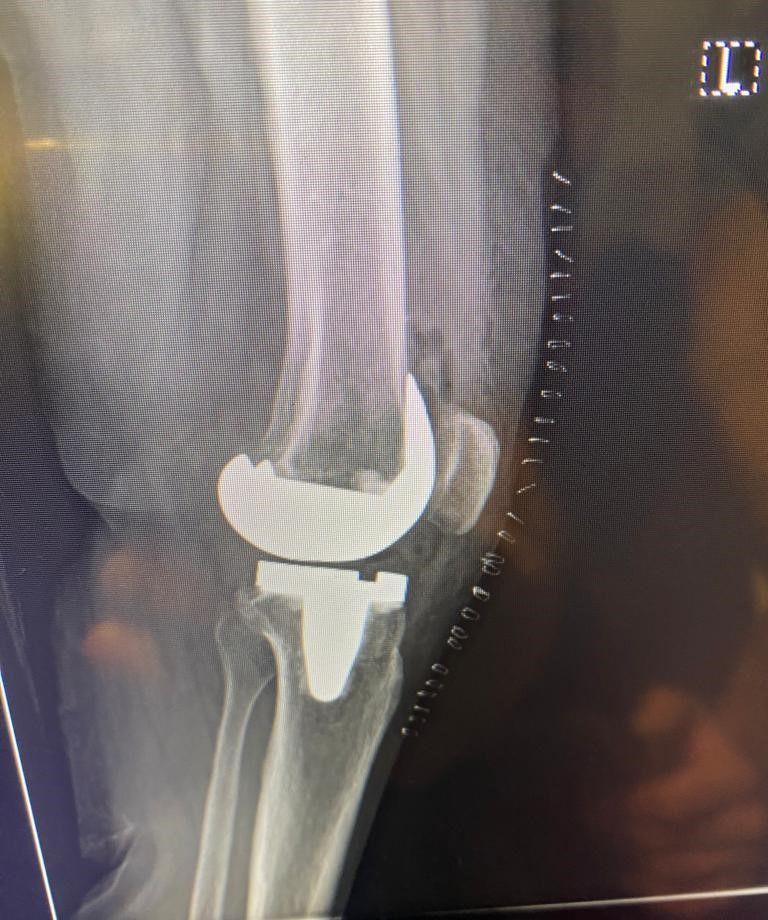

La protesi di ginocchio è costituita da una componente tibiale, una femorale, entrambe in lega di cromo-cobalto, ed un inserto in polietilene che aumenta la congruenza articolare e la stabilità dell’impianto protesico. In genere, le componenti protesiche si fissano all’osso con il cemento, oppure utilizzando degli impianti in tantalio, materiale che si osteointegra completamente entro 3 mesi, senza necessità di cementare.